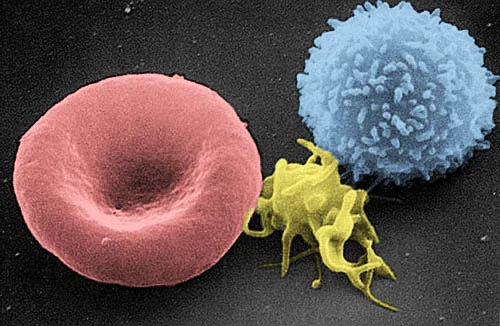

Alcohol suppresses both the innate and adaptive immune systems. R

Chronic alcohol use reduces the ability of white blood cells to effectively engulf and swallow harmful bacteria. R

Excessive drinking also disrupts the production of cytokines, suppresses the development of T-cells, impairs the ability of NK cells to attack tumor cells, and makes you more vulnerable to viruses, bacteria, and cancer. R

Alcohol also makes you more susceptible to contracting HIV and helps HIV develop faster. R

Even if you drink once in a while, alcohol hinders the body's ability to produce necessary cytokines for at least 24 hours. R